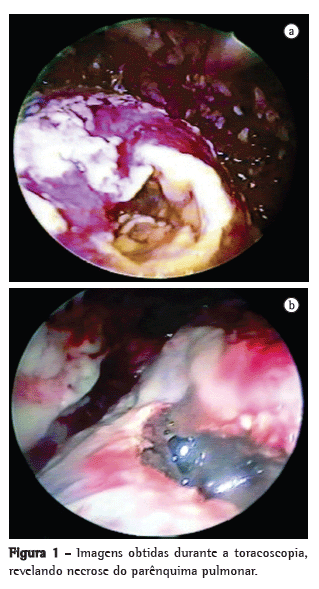

Estabelecia-se o diagnóstico de PN quando uma cavidade contendo detritos necróticos era encontrada no parênquima (Figura 1). Em tais casos, realizava-se desbridamento de todo o tecido necrótico e limpeza, e, para melhorar a drenagem, alargava-se a abertura da cavidade pulmonar.

Necrose do parênquima pulmonar foi encontrada em 24 pacientes (46%).